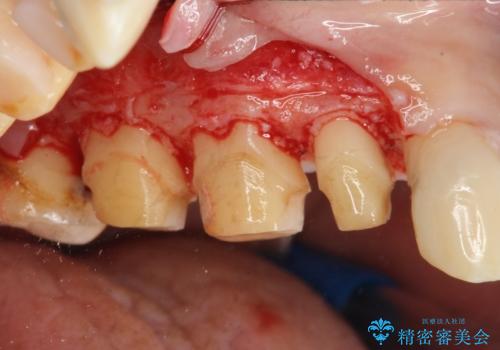

歯周外科で達成する安定したクラウン周囲の歯肉環境

高さが短くなってしまった歯は、安定したクラウンを作るのが難しいため歯ぐきを下げる歯周外科を行ったのちに強度に優れるフルジルコニアクラウンで補綴治療を行います。

すり減ってしまった歯に対し、歯冠長延長術(歯周外科)を行うことで安定したクラウンを製作・装着することが出来ました。